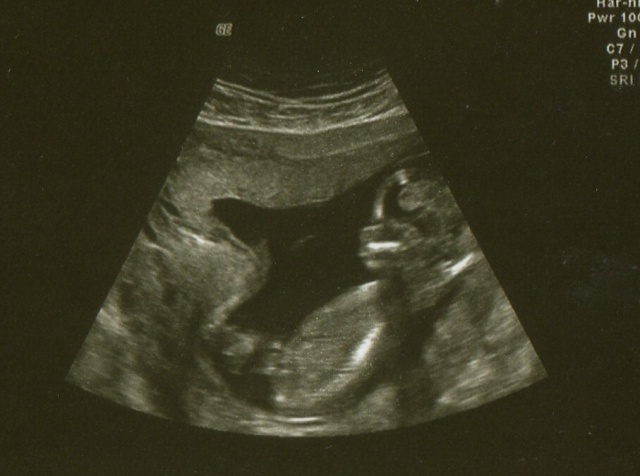

. Tadyk vám dávám zatím jen obrázky mimíska ve 13+3tt a 17+4tt , stromeček a bříško vám sem dám, jak my to manža stáhne ze svého compu do mýho